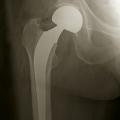

En cas de fracture cervicale vraie Garden III ou IV, le risque de nécrose est important, et il est préférable de s’orienter vers un remplacement prothétique (fig. 14). Il peut s’agir d’une prothèse céphalique où la prothèse remplace uniquement la tête fémorale. Il peut s’agir d’une prothèse intermédiaire qui remplace la tête fémorale mais avec un système de double glissement qui améliore la stabilité de l’implant et diminue les risques d’usure de l’acetabulum. Il peut s’agir d’une prothèse totale de hanche. L’utilisation ou non du ciment pour la fixation de la prothèse ne fait pas consensus dans la littérature, chaque méthode ayant ses avantages et ses inconvénients. Toutefois, chez les patients jeunes, en général de moins de 50 ans, malgré les risques de nécrose, l'ostéosynthèse est conseillée, même dans les fractures Garden III et IV.